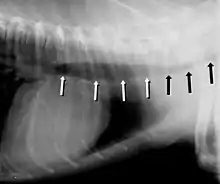

Tracheal collapse

Tracheal stent in a dog

Symptoms include a cough (often called a "goose honk cough" due to its sound), especially when the dog is excited. This cough is usually paroxysmal in nature. Other symptoms include exercise intolerance, respiratory distress, and gagging while eating or drinking. Tracheal collapse is easily seen on a radiograph as a narrowing of the tracheal lumen. Treatment for mild to moderate cases include corticosteroids, bronchodilators, and antitussives. Medical treatment is successful in about 70 percent of tracheal collapse cases.[4] Severe cases can be treated with surgical implantation of a tracheal stent (inside or outside of the trachea) or prosthetic rings. Extraluminal (outside the trachea) stenting is generally used only for tracheal collapse in the neck region. Intraluminal stenting has shown more promise for success with intrathoracic cases, especially using nitinol, a type of shape memory alloy composed of nickel and titanium. Potential problems include stent migration and fracture.[5]